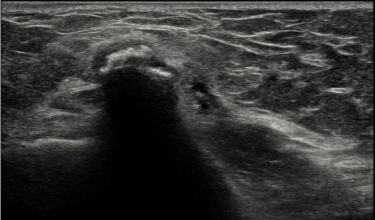

초음파 유도하에 치료 부위 확인하며 주사

PRP주사